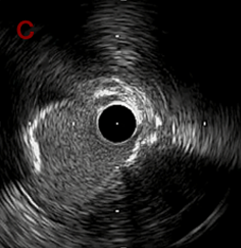

IVUS after OAS low speed 3回

IVUS imaging after low speed 3回

OAS low speedによる引きのsandingを3回行いIVUSを確認するとa-cでは心筋側側へのOASによる良好なbias変化と、それに伴いdの健常側への危険なbias変化を認めた。

そのためcでIVUSマーキングを行い、その点より引きで赤線のpinpoint OAS high speedを行い、dに関してはinjury回避のためにOASを当てない方針とした。